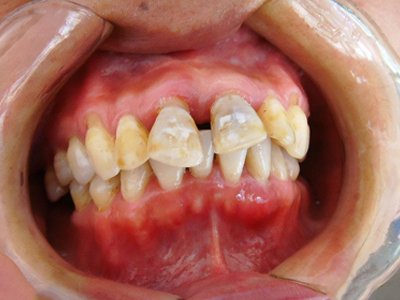

牙龈退缩上牙龈萎缩露出深黄色牙根图

牙龈退缩导致上牙的牙龈严重萎缩,牙根暴露,齿间缝隙大,侧面堆积黄色菌斑。牙龈退缩后根面长久暴露,患者会有牙齿敏感等不适症状。